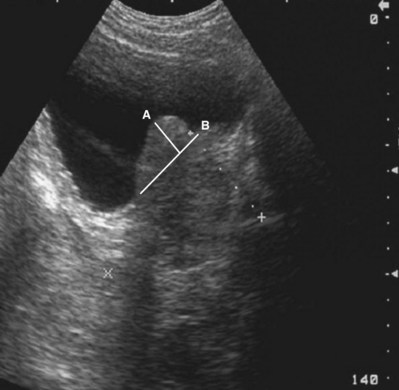

The adult right kidney in the sagittal view demonstrates a cortex that is usually hypoechoic with respect to the liver. The central band of echoes in the kidney is a hyperechoic area that contains the renal hilar adipose tissue, blood vessels, and collecting system. Acoustic shadowing from ribs overlying the inferior pole can be eliminated by moving the probe to a more lateral position or into the intercostal space. By having the patient take a deep breath, the kidney can be moved inferiorly to assist complete imaging (Fig. 4–32).

Figure 4–32 Midsagittal plane of the kidney. Note the relative hypoechogenicity of the renal pyramids (P) compared with the cortex (C). The central band of echoes (B) is hyperechoic compared with the cortex. The midsagittal plane will have the greatest length measurement pole to pole. A perfectly sagittal plane will result in a horizontal long axis of the kidney.